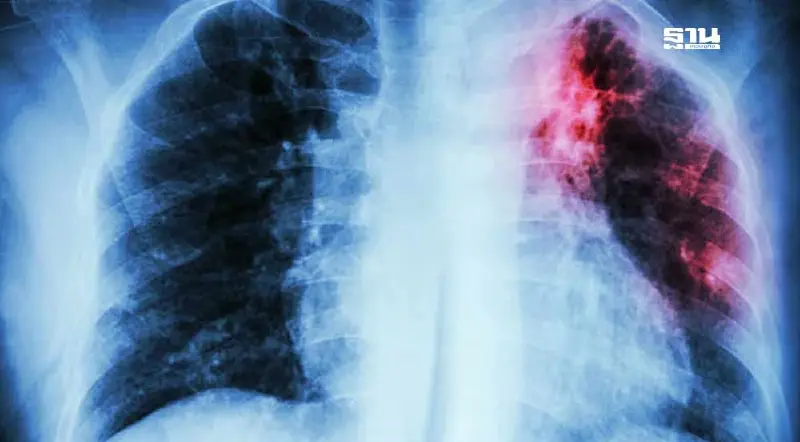

พญ.พวงรัตน์ ตั้งธิติกุล แพทย์เฉพาะทางด้านอายุรศาสตร์โรคระบบการหายใจและภาวะวิกฤตโรคระบบการหายใจ แผนกอายุรกรรม โรงพยาบาลนวเวช กล่าวว่า วัณโรค (tuberculosis) เป็นโรคระบาดยังพบมีการกระจายอยู่ในประเทศไทยและหลายประเทศทั่วโลก เกิดจากเชื้อแบคทีเรีย (Mycobacterium tuberculosis)

เมื่อผู้ป่วยวัณโรคปอดไอ จาม พูดดัง ๆ ตะโกน หัวเราะหรือร้องเพลง ทำให้เกิดละอองฝอย (droplet nuclei) ฟุ้งกระจายออกมา จนผู้อื่นสูดหายใจเอาละอองฝอยที่มีเชื้อวัณโรคเข้าไปสู่ถุงลมในปอด จะทำให้เกิดอาการผิดปกติที่เกี่ยวข้องกับระบบทางเดินหายใจ ซึ่งหลายคนมักคุ้นเคยในชื่อ “วัณโรคปอด”

พญ.พวงรัตน์ กล่าวว่า สำหรับผู้ที่สัมผัสผู้ป่วยและอยู่ในกลุ่มเสี่ยงสูง ควรพบแพทย์เพื่อตรวจคัดกรองอาการ และเอกซเรย์ปอดโดยเร็วที่สุด ได้แก่